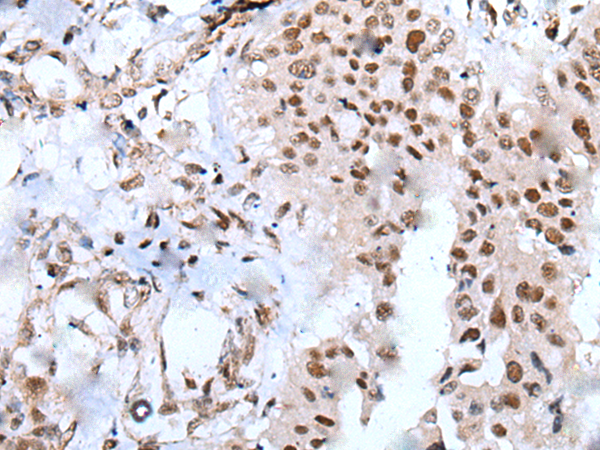

分类: 科研抗体货号: P05984别名: ZNF631应用: IHC反应种属: Human